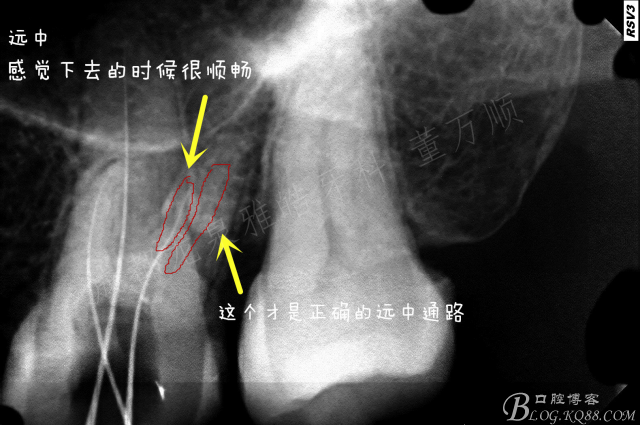

第一次简单去除原充填物 疏通了一下根管 鄂根还是非常顺利的下去了,远中只能下去一点点,近中没有发现根管口迹象。

复诊的时候 着重去寻找近颊根,配合超声,此时一定要有耐心,慢慢的8号挫有感觉了

照插针片的时候 感觉远颊下去的时候 瞬间有落空感,伴有轻微疼痛

一看牙片,坏了,肯定是侧穿了,心情平和一下,封药,改约时间下次预备

按时复诊 ,过程你懂的 8号挫预弯,找啄歰感 配合牙片,1次 2次 3次......

经过半个小时努力总算是找到了 预备,荡洗 根充。